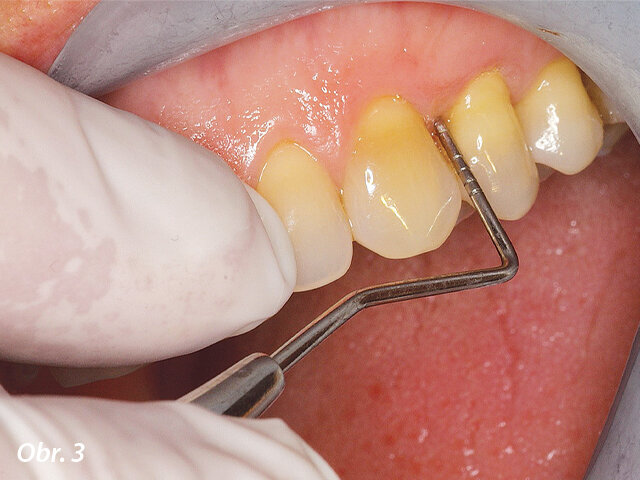

Parodontologická sonda v ošetřené oblasti: nebyla prokázána přítomnost parodontálních kapes a pacientka byla schopna opět řádně pečovat o své ústní zdraví.